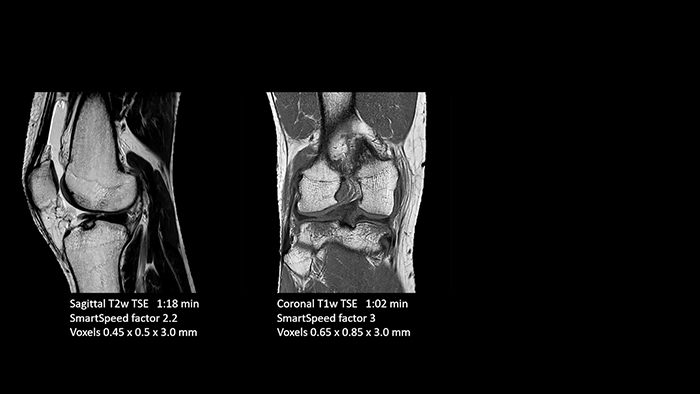

A leap in MSK imaging thanks to SmartSpeed

Previously, the practice wasn’t able to use 3D imaging on all joints, because the time required was too long, and on some joints it was simply not possible to achieve a good quality image, Dr. Schröter says. “Now, with SmartSpeed we consistently use 3D imaging for all joints and can thus discover the smallest changes, for example in the cartilage. And that, of course, helps us in making a detailed diagnosis.”

Dr. Schröter says their MSK images show high contrast and extremely high quality. He mentions the menisci as an example. “We use a 3D proton density weighted fatsat sequence, thickness is 0.3 mm and scan time 3 minutes. The MPRs show an unbelievable resolution. Very small tears and even fraying of the tip of the meniscus become visible, which is normally only possible in arthroscopic surgery.

“Thanks to SmartSpeed, we are able to perform examinations extremely quickly. We can carry out most examinations in under ten minutes. Our MRI exam of the knee only takes six minutes. The shorter time makes it easier for patients to lay still, which helps prevent motion artifacts.

Then, because the computing capacity is so large, we have the images immediately available on the large screen. Higher resolution is very valuable. From the high-resolution 3D sequences, excellent multiplanar reconstruction can be obtained. This makes it easier and faster for us to diagnose and create reports. And while the patient is still lying in the magnet, we can already view the images and make a diagnosis. When the patient comes out, I can immediately ask whether what I see corresponds to the symptoms.”